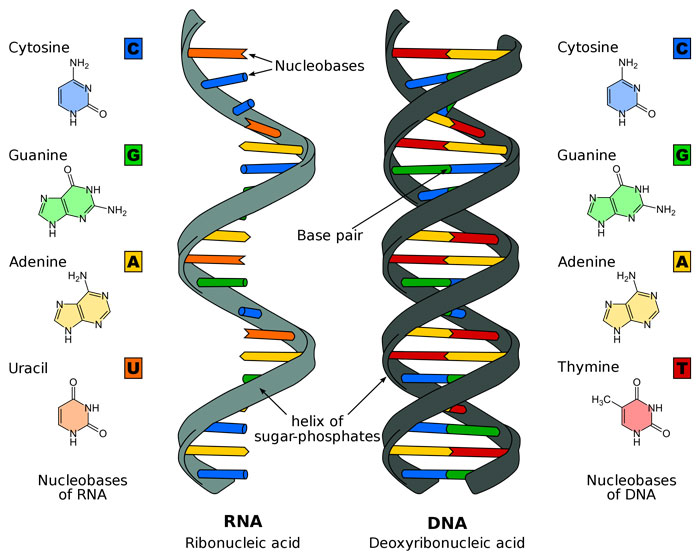

قیمت: 52٬000 تومان - دسته بندی فایل: پاورپوینتپاورپوینت نوکلئوتیدها ساختمان DNA ساختمان RNA

فروش ویژه پاورپوینت حرفه ای نوکلئوتیدها ساختمان DNA ساختمان RNA با تخفیف استثنایی فقط 49 هزار تومان تعداد اسلاید : 30 اسلاید